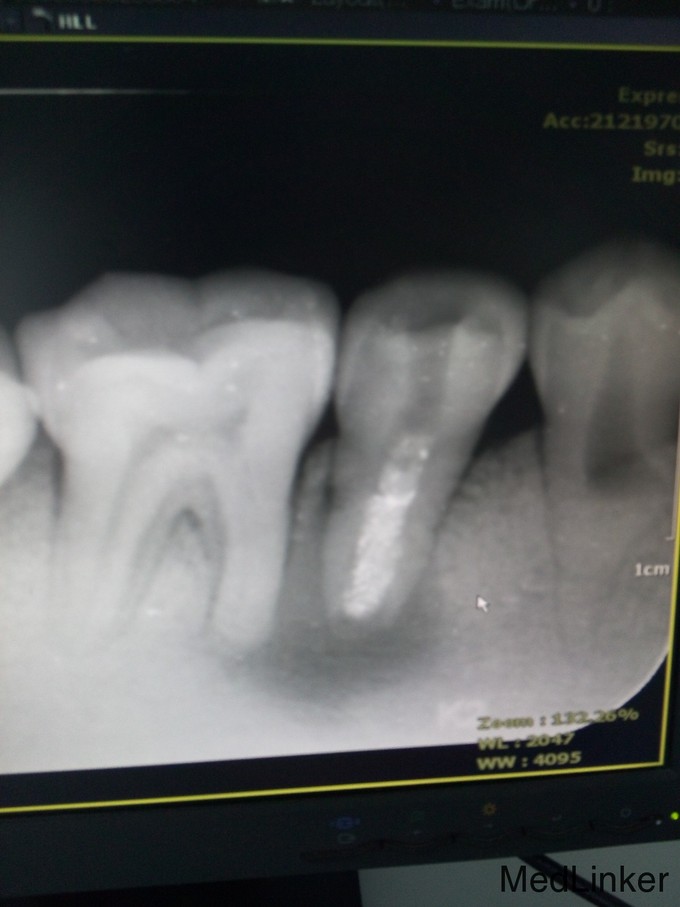

女,27岁 右下后牙不适,要求治疗 患者3月前右下后牙出现隐痛,于外院治疗,反复封药,症状缓解。外院建议拔除,现来我科就诊。

检查:45牙可见开髓口,叩(+-),未见松动。34、35、44牙可见畸形中央尖。 影像:45牙根尖可见大面积低密度影。

45牙根尖周炎 34、35、44牙畸形中央尖 治疗计划 45牙行根管治疗? 34、35、44牙定期复查 处置:去除原有封药,超声反复荡洗,冲洗清理根管后封VITA,三月后复诊,制定后续治疗计划。